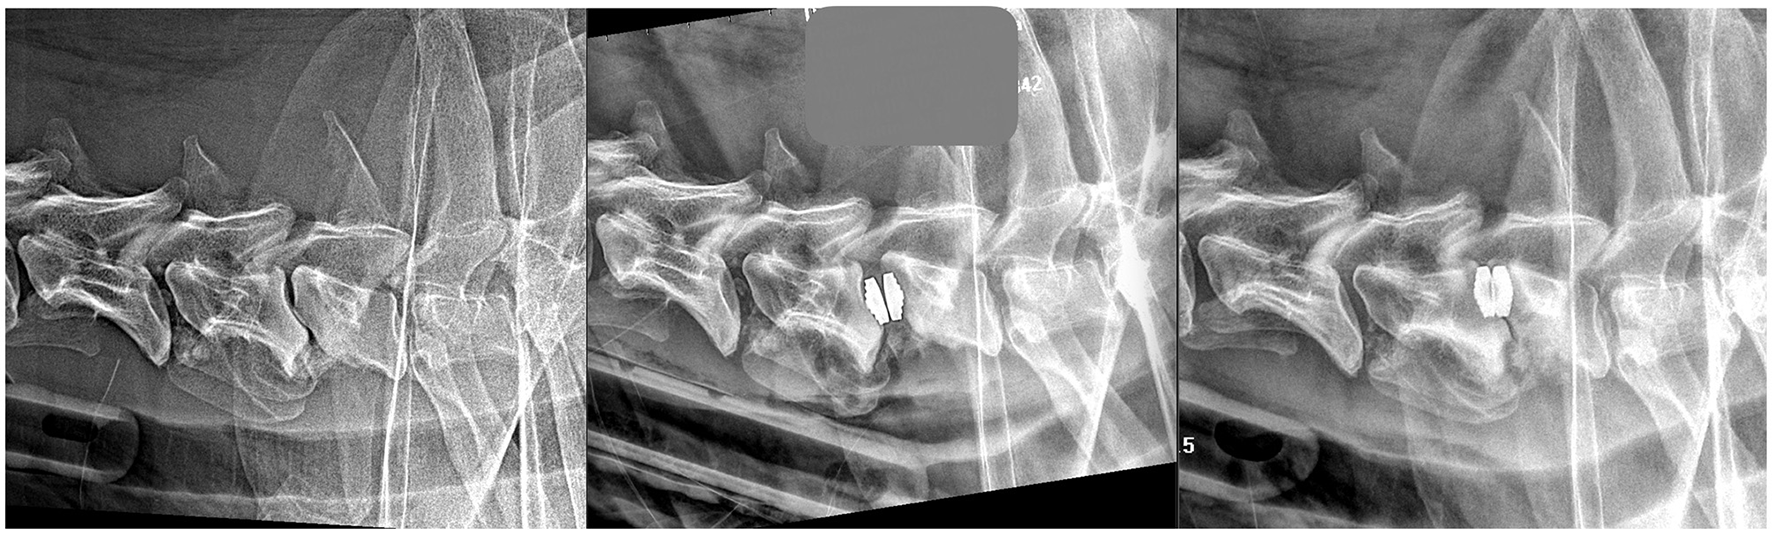

Radiographs were taken immediately post-operatively, and at 1 and 3 months after surgery (Figures 1, 2) for evaluation. Radiographic evaluation mostly focused on subsidence, described as the percentage of distraction loss between the dorsal aspect of the adjacent treated vertebral endplates. Two authors separately measured the distance between the two dorsal aspects with open-source software for navigating multidimensional DICOM images (Osirix, www.osirixviewer.com) at the time of surgery and follow-ups. Distraction loss between immediate post-operative and follow-up radiographs was calculated as a percentage. Subsidence was rated as mild (10 and 25% distraction loss), moderate (25–50%), severe (more than 50%), and none (0–10%, as a minimum human margin of error was considered possible and acceptable). The degree of vertebral fusion/bone production among the dogs treated with DS and the degree of residual motion among the dogs treated with PD were also considered using dynamic X-rays (neutral, flexed, and the dorsal extended position of the cervical column). Other changes, such as breaking of a screw or signs suggestive of discospondylitis were also noted. MRI images were repeated at different times after surgery. Implant position, residual cord compression at the treated sites, new sites of cord compression, vertebral collapse or changes, such as bone lysis, and intra-medullary changes, such as parenchymal hyperintensity on T2 weighted images, were evaluated. Furthermore, parenchymal hypointensity on T1 weighted images was reported.

Radiographic Outcomes

All the dogs were radiographed immediately post-operative. Radiographs were repeated in 23 dogs, from 30 to 90 days. Four of these 23 dogs also had extra radiographs at 6 months and 2, after 1 year. Two dogs were lost to medium-term radiographic follow-up: the DS-dog that had died unexpectedly and one PD-dog where the owner declined imaging. Of the 23 dogs available for radiographic evaluation, subsidence was identified in 11/12 dogs in the PD group and 7/13 dogs in the DS group. In the 11 dogs in the PD group, subsidence was more evident over time and varied from mild in four patients, to moderate in three dogs, and severe in four cases (Table 1). As previously stated, the two dogs with disc extrusions had moderate subsidence. The dog in the PD group that deteriorated after 9 days had severe subsidence: this dog was reoperated by the DS technique. The remaining three cases with severe subsidence had significant new bone production in the treated sites 90 days after radiographic reassessment. In one dog, almost complete vertebral fusion was detected (Figure 4). In contrast, in two dogs, a mild residual vertebral movement was evident on the flexion and extension radiographs. Of these three dogs, one was neurologically unchanged compared to their pre-operative assessment, while two deteriorated clinically, with neck pain in both cases and mild tetraparesis in one dog. These dogs were treated conservatively, with partial improvement. In the PD group, the degree of vertebral motion evaluated in the flexed and extended neck position was preserved in only one dog with mild subsidence, while it decreased to absent in the remaining dogs in proportion to the severity of subsidence. A high tendency for vertebral fusion with new bone production and spondylosis was radiographically more evident in cases of moderate and severe subsidence.

Figure 4. Latero-lateral radiographs of the same dog before a PD surgery (left image), at 30 days post-op (middle image) and at 90 days post-op (right image).